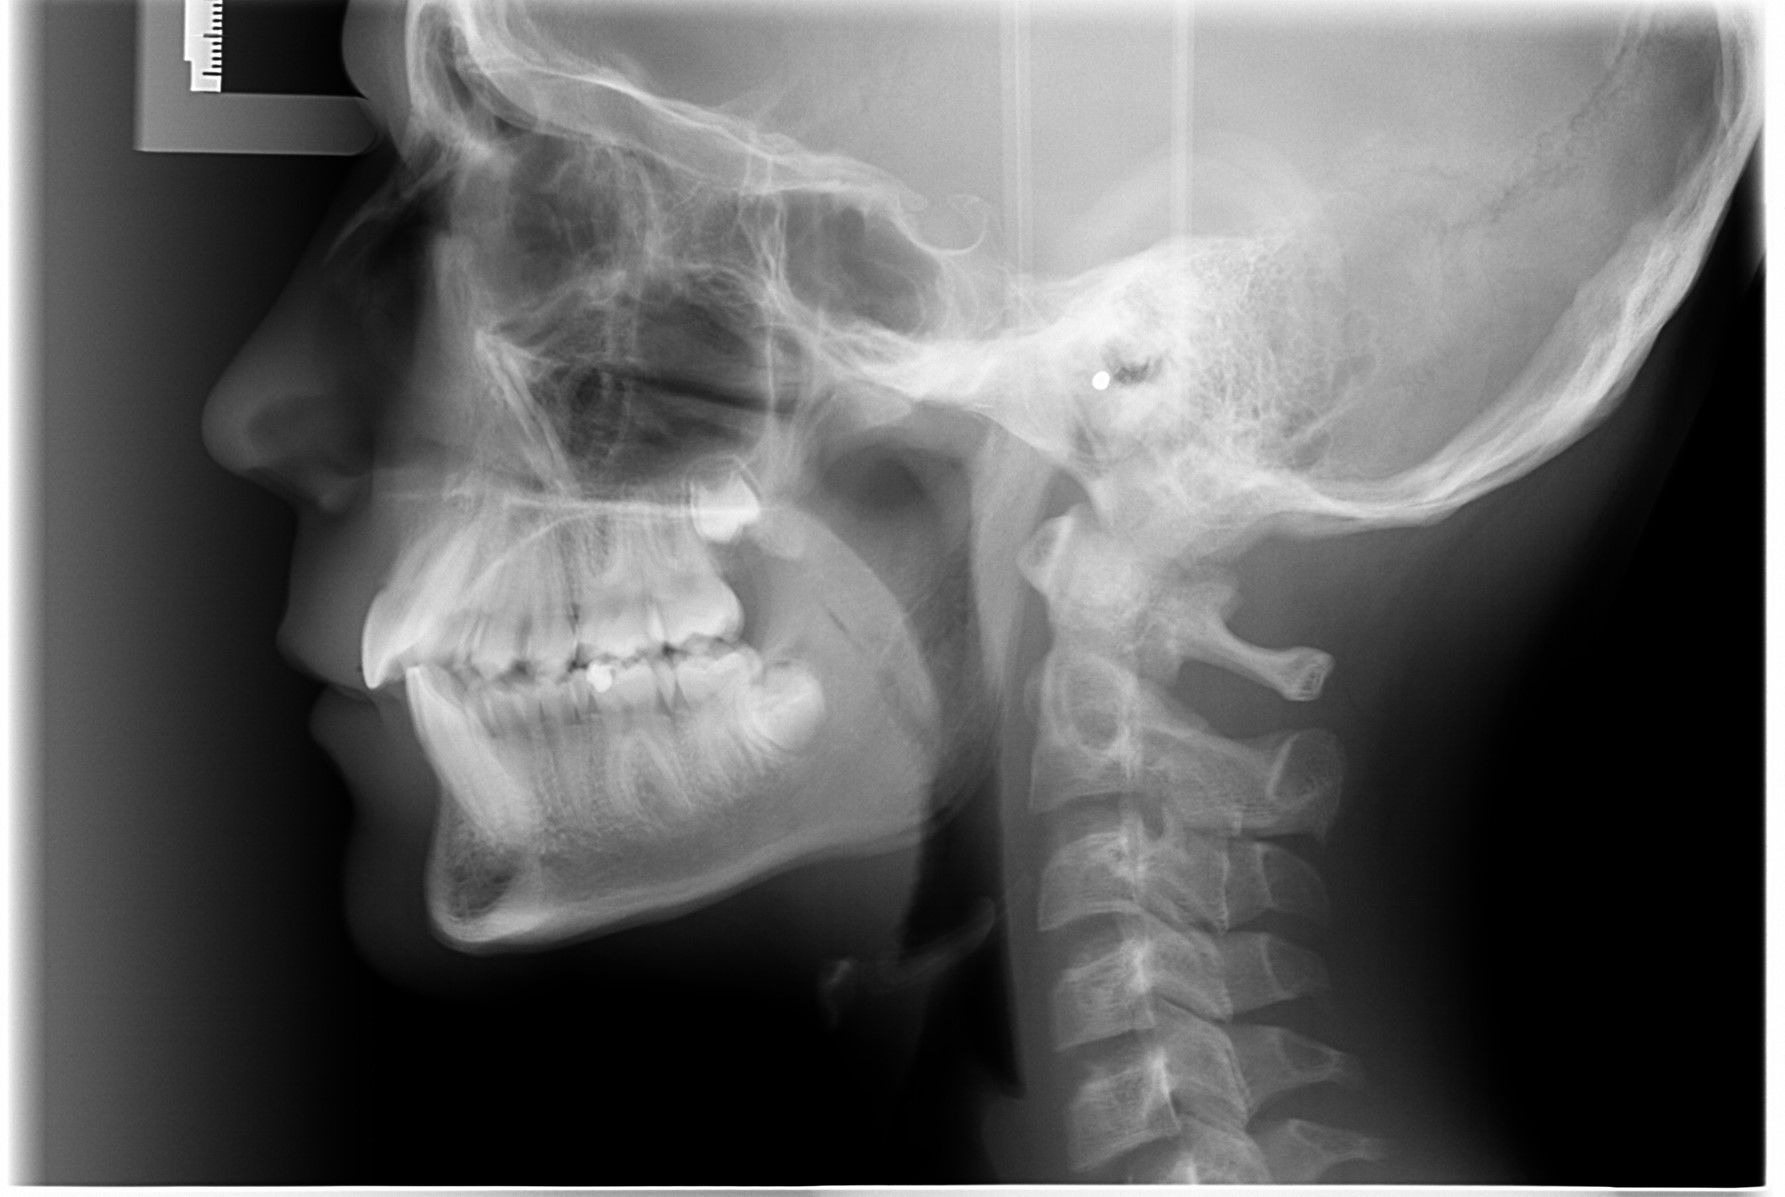

- Vi tager røntgenbilleder af tænder, kæber og hoved.